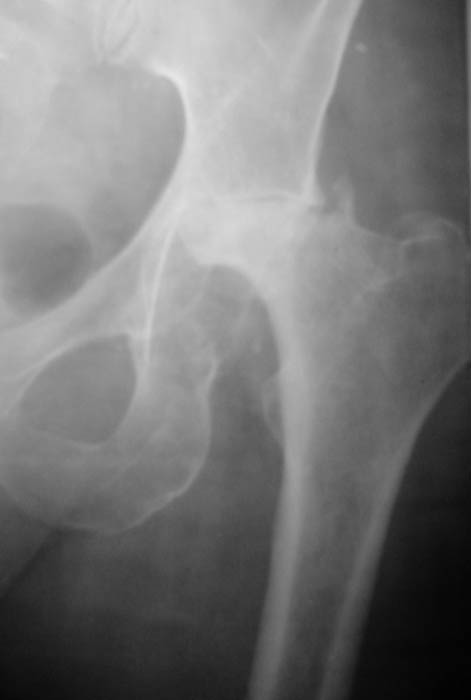

Уважаемые коллеги! Прошу Вас оказать консультативную помощь. Женщина, 44 года, инвалид 3 группы Диагноз: СКВ, асептический некроз головок обеих бедернных костей, двусторонний артроз 3-4 ст., болевой синдром, приводящая контрактура правого тазобедренного сустава,

хронический волчаночный гепатит, спленомегалия, анемия, СКВ с 2002 года (подтверждена наличием lupus-клеток), получала специфическую терапию, медрол 16 мг/сут. Боли в левом тазобедренном суставе появились в сентябре 2003 года. Динамика отражена на рентгенограммах. В марте 2004 года - синдром Мэллори-Вейса, кровотечение остановлено эндоскопически.

Ходит с тростью, хромота. Объем движений в суставах: справа - сгибание 90, разгибание 170, отведение 0, приведение 20, внутренняя ротация 15; слева - сгибание 90, разгибание 180, отведение 0, приведение 20, внутренняя ротация 0, наружная ротация 20.